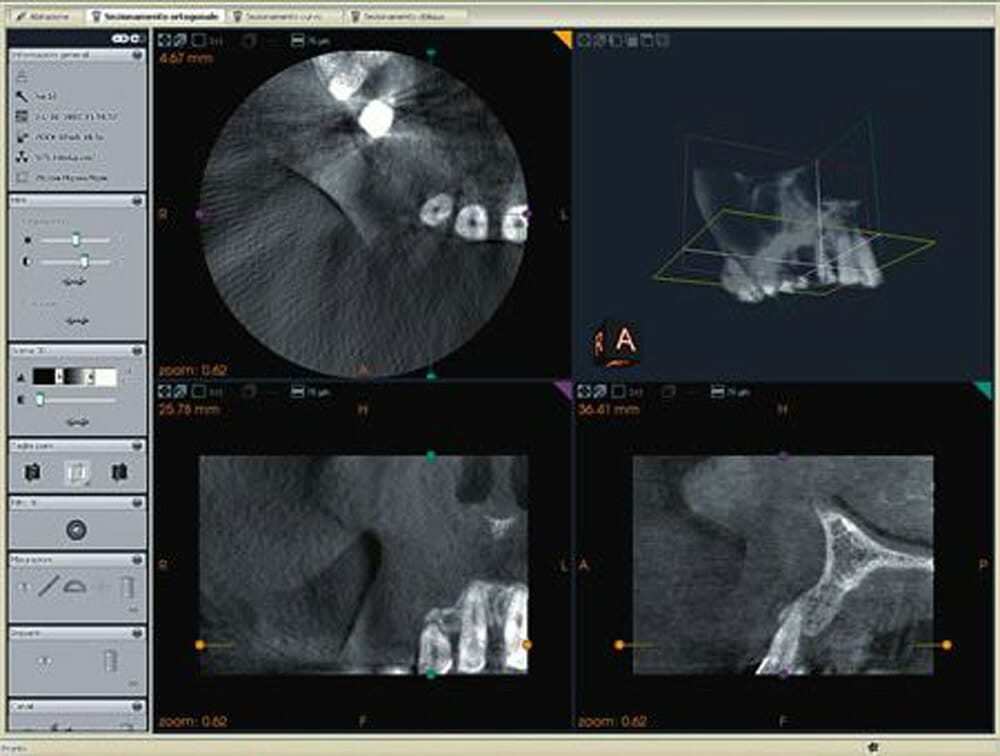

- Cone Bean o radiografia digitale 3D: è un elemento ormai imprescindibile in campo dentistico e si utilizza per la chirurgia implantare, l’endodonzia, il trattamento conservativo e l’estrazione dei denti. Le immagini Cone Bean riproducono fedelmente e in maniera tridimensionale l’anatomia del paziente, permettendo di osservarne le dimensioni da qualunque punto di vista così da avere una visione completa.

Grazie ad apparecchi e sensori di ultima generazione, la dose di radiazione assorbita è innanzitutto estremamente più bassa rispetto a quella dei sistemi tradizionali. Inoltre, i nostri sofisticati software di gestione ci permettono di valutare l’immagine radiografica ingrandendola, ruotandola, osservandola tridimensionalmente, colorandola a seconda della densità dei tessuti, e misurandone le dimensioni.